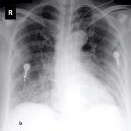

The COVID-19 disease was first discovered in Wuhan, China, and spread quickly worldwide. After the COVID-19 pandemic, many researchers have begun to identify a way to diagnose the COVID-19 using chest X-ray images. The early diagnosis of this disease can significantly impact the treatment process. In this article, we propose a new technique that is faster and more accurate than the other methods reported in the literature. The proposed method uses a combination of DenseNet169 and MobileNet Deep Neural Networks to extract the features of the patient's X-ray images. Using the univariate feature selection algorithm, we refined the features for the most important ones. Then we applied the selected features as input to the LightGBM (Light Gradient Boosting Machine) algorithm for classification. To assess the effectiveness of the proposed method, the ChestX-ray8 dataset, which includes 1125 X-ray images of the patient's chest, was used. The proposed method achieved 98.54% and 91.11% accuracies in the two-class (COVID-19, Healthy) and multi-class (COVID-19, Healthy, Pneumonia) classification problems, respectively. It is worth mentioning that we have used Gradient-weighted Class Activation Mapping (Grad-CAM) for further analysis.

翻译:COVID-19 疾病在中国武汉首次发现,并迅速蔓延到全世界。在COVID-19 流行病后,许多研究人员开始寻找一种方法,利用胸前X光图像诊断COVID-19 。早期诊断该疾病可以大大影响治疗过程。在本篇文章中,我们提出了一种比文献中报告的其他方法更快和更准确的新方法。拟议方法使用DenseNet169 和移动网络深神经网络的组合来提取病人X光图像的特征。在使用单向特征选择算法后,我们改进了最重要的特征。然后,我们将选定特征用作对光GBM(轻度推动机)算法的投入。为评估拟议方法的有效性,使用了ChestX-光8 数据集,其中包括病人胸部的1125 X光图像。拟议方法在两类(COVID-19,健康价值)和多级(COVID-19)中达到了98.54%和91.11%的缩略图。我们分别使用了“高度”的GRAMA-GRA级(C) 分别用于健康等级分析。